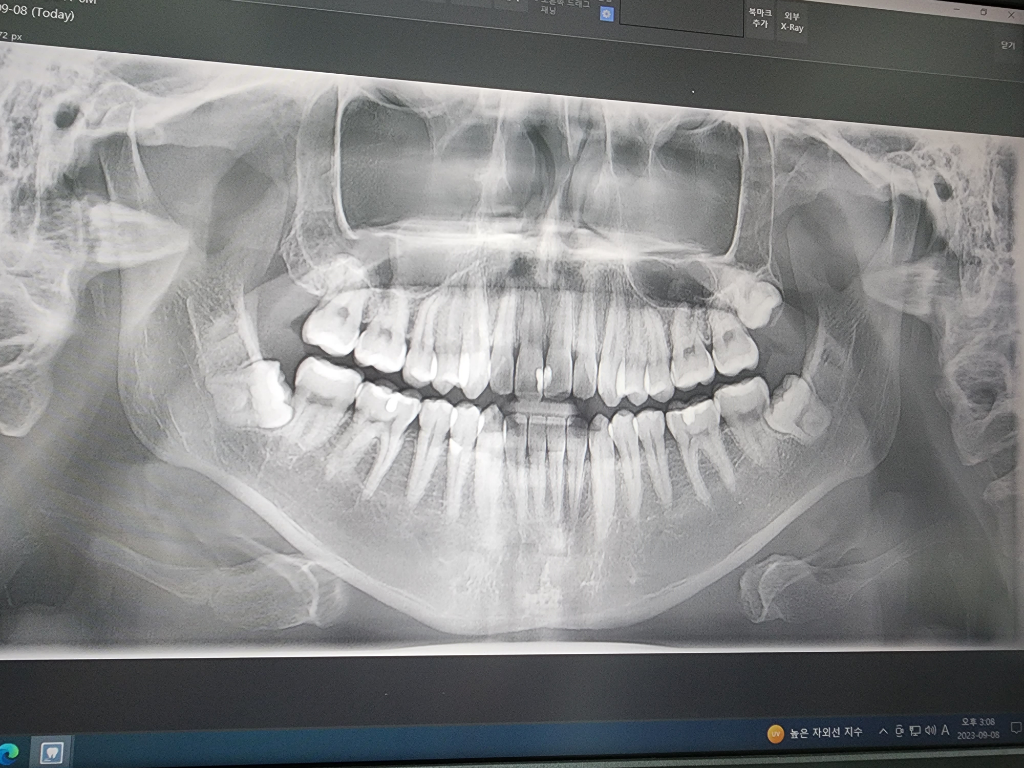

1. 방사선 사진상 위 사랑니의 경우 아직까지 더 맹출할 여력이 있습니다. 보통 20대 초중반까지 위 사랑니는 뼈나 옆 어금니에 걸려있지 않은이상 내려옵니다.

2. 아래 사랑니의 경우 신경을 누르고 있다고 하셨지만 그건 ct를 찍어봐야 정확히 알 수 있고 신경관에 매우 근접하게 사랑니가 위치하고 있는 것은 맞습니다.

3. 아래 사랑니 둘다 옆에 어금니를 밀고 있으므로 옆 어금니의 뿌리 흡수나 충치 가능성이 있습니다. 발치를 하지 않는다 하더라도 이런점이 있음을 알고 계셔야 합니다.